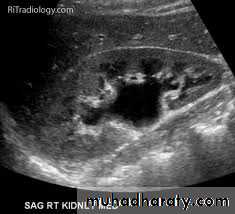

1-Dilatation of the P.C.S. appears as multilocular fluid collection within central echo complex.

-With more severe distention, dilated calyces appear as

Multiple cysts but communicating with each other unlike true cysts.